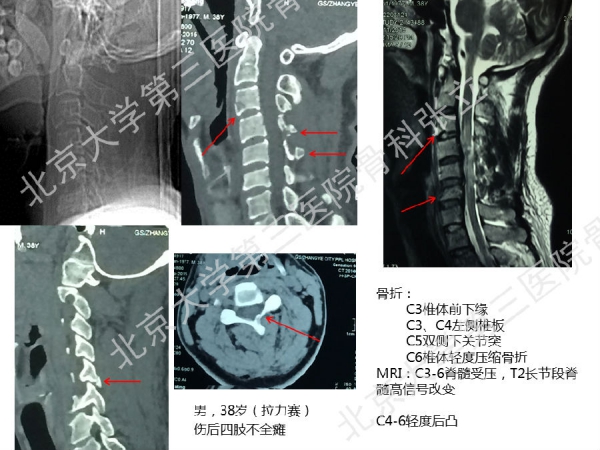

徒手置钉的下颈椎椎弓根钉技术对于很多骨科同道来说,无疑是难度超高、不敢触及的一项技术。已熟练掌握这一技术的北京大学第三医院骨科张立主任医师认为,下颈椎椎弓根钉徒手置钉技术固定可靠,能满足绝大多数后路固定所需,可应用于脊柱外伤、脊柱畸形、脊柱肿瘤,以及CSM伴退变性颈椎后凸畸形。它的优势是:螺钉尾部靠外,不影响椎板成形术;先置钉固定,后开门,更安全;和椎板成形术完美结合,减压、复位、固定一次完成;极少出现脊髓、神经根及椎动脉损伤。